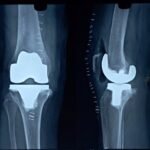

The MISSO robotic arm allows accurate placement of components during hip and knee replacement procedures. The use of these technologies enables the surgeon to perform minimally invasive hip and knee replacement with increased surgical precision and minimal soft tissue injury. This translates into shorter hospital stays, less pain, and faster recovery for patients.

The robotic arm is a tool that is used to place implants accurately and precisely. The implants used for hip and knee replacement have been in the market for decades and have good long term survivorship data. For most patients, the implants should last for the rest of their lives.

Bone cuts are more as compared | Minimum bone cuts |

Femoral canal need to b opened | Femral canal not opened |

Less bone preserved | More bone preserved so longevity of implants remain longer |

Implant position less options | Femoral component can be placed in varus, valgus, internal external rotation, anterior and distal upward downward, in flexion extension |